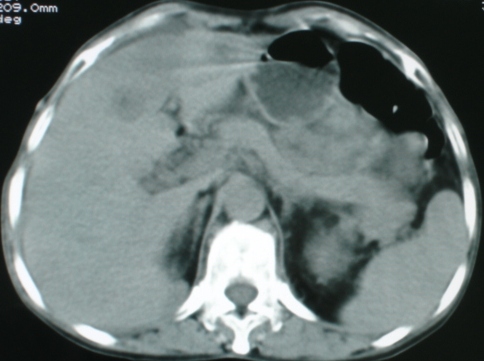

以下是引用zsl6918在2008-11-4 19:14:00的发言:[br]多发转移性改变,子宫改变不除外为原发灶